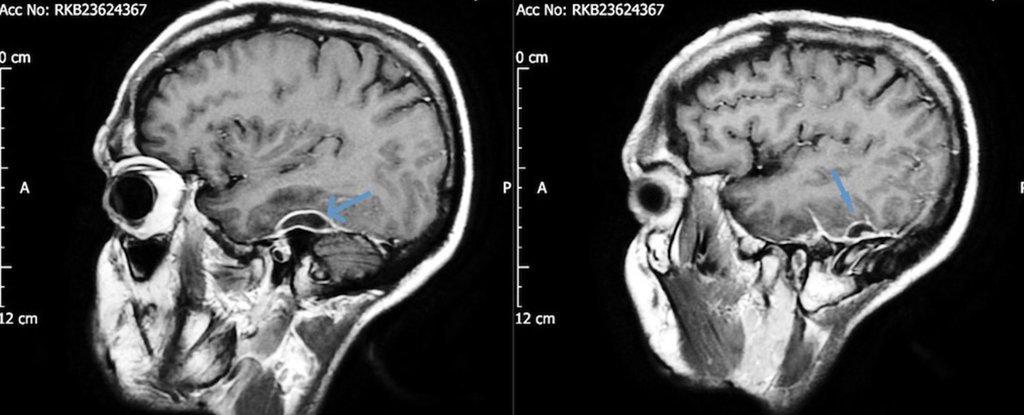

Limpiarte los oídos con cotonetes podría causarte un gran daño. Así lo indica la revista médica BMJ Case Reports, que recientemente publicó el caso de un hombre de 31 años que por el uso reiterado de estos objetos terminó con una grave infección en el tejido que rodea el cerebro. Según publicó la revista, el hombre llegó al hospital con convulsiones y estuvo a punto de sufrir un colapso. Los primeros exámenes físicos que le realizaron, mostraron que el paciente presentaba confusión, adormecimiento y un estado alterado de conciencia. El sujeto indicó a los médicos que en días anteriores presentó dolores de cabeza y dificultad para recordar nombres. Lo más inquietante fue que el hombre relató que durante cinco años padeció un dolor intermitente en el oído izquierdo y estaba perdiendo la audición. Cuando los médicos realizaron una tomografía, encontraron en el paciente abscesos en el tejido que rodeaba su cerebro. La bacteria culpable de la infección fue la Pseudomonas aeruginosa, un patógeno que causa todo tipo de enfermedades y que ocasionó otitis extrerna necrotizante dañando el tejido que se encuentra en el canal auditivo externo. Esta bacteria llegó al cráneo a través de un pedazo de algodón que formaba parte de un cotonete, el cual se había quedado atascado en la cabeza del paciente durante años. Tras extraer el pedazo de algodón, la bacteria fue eliminada con antibióticos, lo que permitió que se resolvieran los problemas neurológicos del paciente. Así que ahora ya lo sabes: antes de meterte algo en los oídos o limpiarlos, recuerda las complicaciones que esto te puede ocasionar.